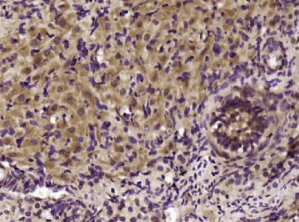

多聚甲醛固定,石蜡包埋(大鼠卵巢组织);用柠檬酸钠缓冲液(pH6.0)煮沸15min后获得抗原;用3%过氧化氢阻断内源性过氧化物酶20分钟;阻断缓冲液(正常山羊血清)37℃30min;用(BAG1)聚氯乙烯进行抗体孵育未结合的Al抗体在1:400下在4°C下过夜,然后根据SP试剂盒(兔子)说明和DAB染色进行操作。